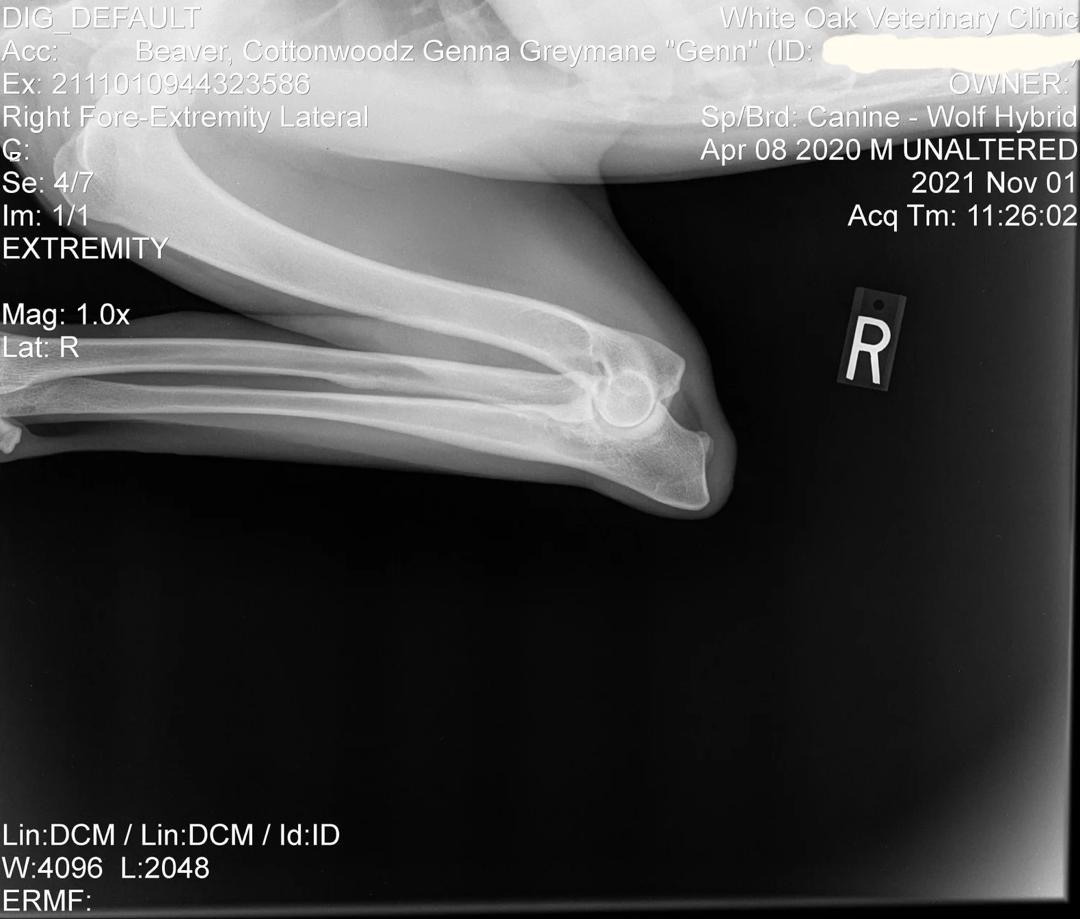

Genn Preliminary Right Elbow X-Ray

Preliminary Right Elbow X-Ray

Early evaluation: Normal formation